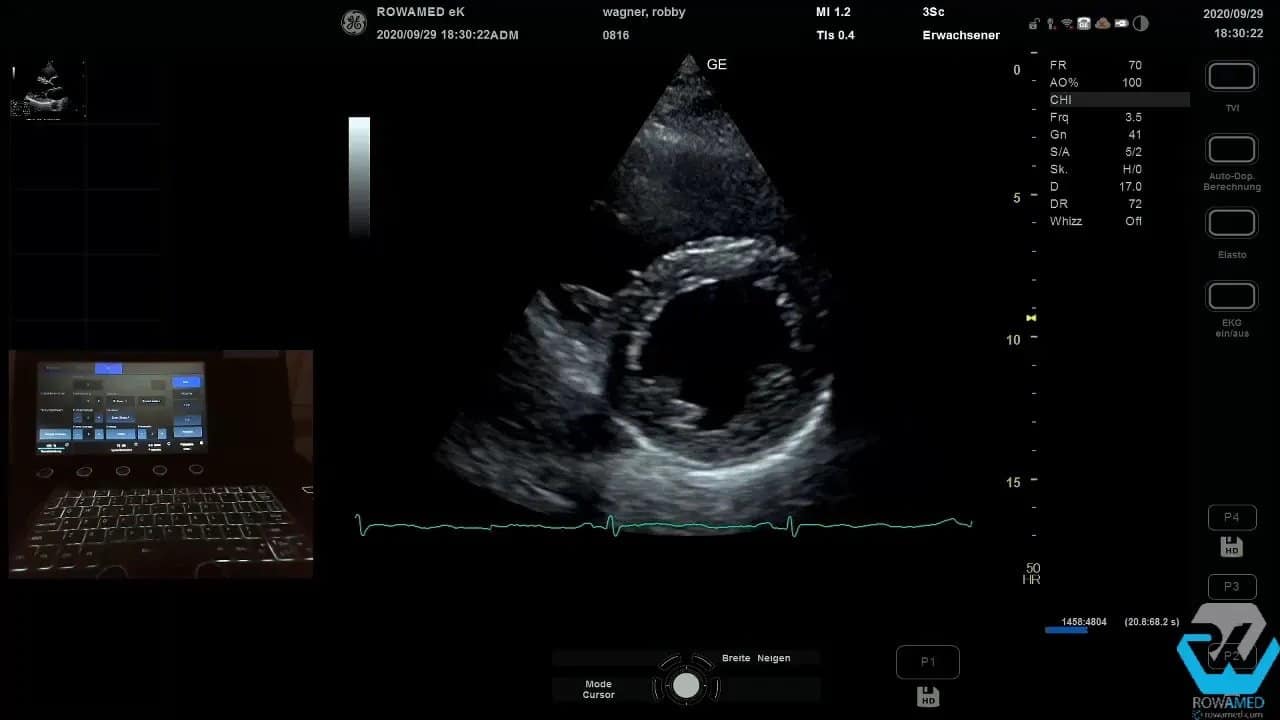

Step 4: In die parasternale kurze Achse wechseln

Als Nächstes folgt die parasternal kurze Achse. Auf mittventrikulärer Höhe sehen Sie den linken Ventrikel zirkulär, häufig mit den beiden Papillarmuskeln als runde Landmarken. Diese Ebene ist hervorragend geeignet, um die konzentrische Kontraktion des linken Ventrikels zu beurteilen.

Hier lässt sich rasch erkennen, ob die Kinetik insgesamt normal ist. Das ist besonders dann hilfreich, wenn Sie die visuelle Einschätzung später mit Volumen- oder EF-Messungen ergänzen wollen.

Durch weiteres Kippen des Schallkopfs nach kranial erreichen Sie zunächst die Mitralklappenebene und dann die Herzbasis mit der Aortenklappe. In dieser Projektion beurteilen Sie die Aortenklappe morphologisch sehr direkt. Im gezeigten Fall war sie trikuspide, also regelrecht aus drei Taschen aufgebaut, und öffnete sich gut.

Damit ist die parasternal kurze Achse in der Transthorakale Echokardiographie nicht nur eine Zusatzebene, sondern ein echter Baustein für Funktions- und Morphologiediagnostik.